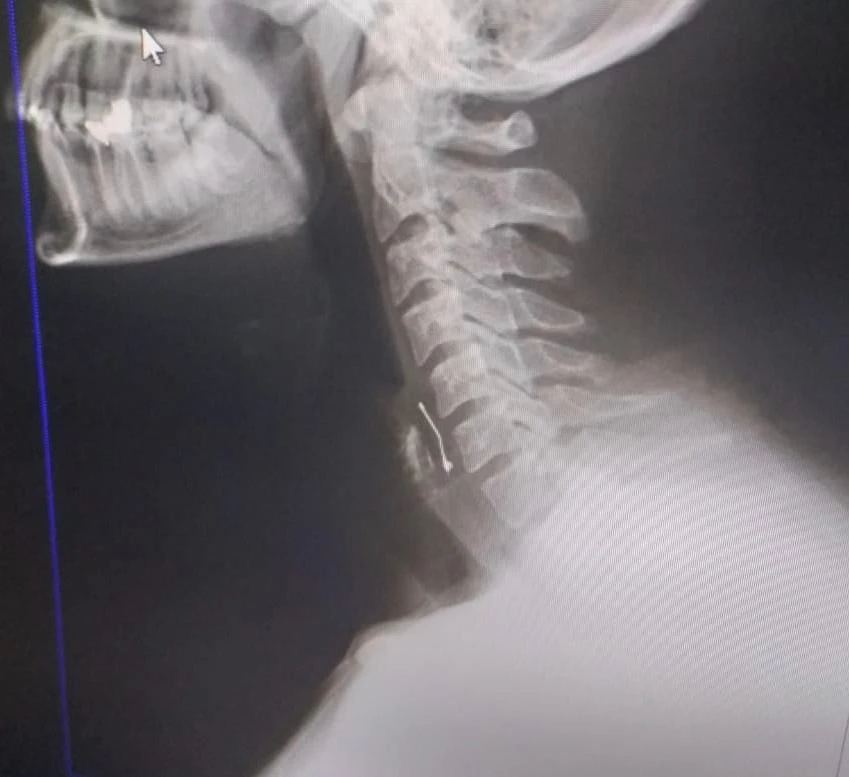

Edinilen bilgiye göre, arkadaşının doğum gününü kutlamak için Tekerek mevkisinde bir pastaneye giden Ramazan Orçan (22), pastayı yedikten sonra fenalaşınca Kahramanmaraş Sütçü İmam Üniversitesi (KSÜ) Tıp Fakültesine götürüldü. Yapılan kontrollerde boğazına toplu iğne saplandığı tespit edilen genç, acil ameliyata alındı. Ameliyatla boğazına saplanan iğne çıkarılan Ramazan Orçan’ın tedavisi sürüyor.

Ramazan Orçan, “Perşembe akşamı arkadaşlarımla birlikte Tekerek’te bulunan bir pastaneye doğum günü kutlamak için gittik. Biraz oturduktan sonra yaş pasta masamıza geldi. Ben pastadan birkaç defa aldım. Boğazıma bir şeyin battığını ve nefes alamadığımı hissettim. Acil olarak pastaneden ayrıldık ve Kahramanmaraş Sütçü İmam Üniversite Acil Servisine geldik. Burada yapılan tetkikler sonucu boğazımda bir toplu iğne olduğu kanısına varıldı. Defalarca operasyon geçirdim. Yoğun uğraşlar sonucunda toplu iğne boğazımdan çıkarıldı. Şuan hastanede yatıyorum. Bir süre daha gözetim altında tutulacağım. Ölümle kalım arasında kaldığımı doktorlar ifade etti. Benim başıma geldi, başkalarının başına gelmesin. Olayı yargıya taşıyacağım” dedi.